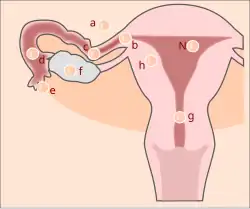

Ovários, trompas de Falópio e vagina

O corpo lúteo, que normalmente se desintegra no fim do ciclo menstrual e dá origem à menstruação, é, em caso de gravidez, preservado por hormonas segregadas pela recém-formada placenta. Isto acontece porque o corpo lúteo produz duas hormonas essenciais à gravidez, a progesterona e o estrogéneo, e só após algumas semanas é que a placenta é capaz de produzir estas hormonas de forma autónoma e sem colocar em risco a gravidez. Durante os primeiros meses, o ovário onde se situa o corpo lúteo em funcionamento é consideravelmente maior, normalmente regredindo no fim da gravidez. O papel das trompas de Falópio na gravidez restringe-se à alimentação do zigoto enquanto se desloca entre o ovário e o útero. Ao longo da gravidez, a cor geralmente rosada da vagina altera-se para um tom azulado devido à dilatação dos vasos sanguíneos e, mais tarde, para vermelho devido à maior afluência de sangue. O número e o tamanho das células da mucosa vaginal aumentam, produzindo maior quantidade secreções. A superfície torna-se mais macia, flexível e relaxada com o objetivo de preparar a passagem do feto durante o parto.[1]

Útero e placenta

O útero é um órgão de forma semelhante a uma pêra, que compreende uma extremidade inferior, denominada colo do útero (ou cérvix), adjacente a uma parte bolbosa maior, denominada corpo do útero. Numa mulher não grávida com cerca de vinte anos, o útero mede aproximadamente sete centímetros de comprimento e pesa cerca de 30 gramas. No termo de uma gravidez, o útero mede cerca de 30 cm de comprimento, pesa cerca de 1 200 g e tem uma capacidade líquida entre 4 e 5 litros. Este aumento significativo de tamanho durante a gravidez deve-se ao aumento da quantidade de fibras musculares, vasos sanguíneos, nervos e vasos linfáticos na parede uterina. A própria fibra muscular aumenta entre cinco a dez vezes de tamanho e o diâmetro dos vasos sanguíneos e capilares aumenta consideravelmente. Durante as primeiras semanas de gestação, a forma do útero mantém-se inalterada. Por volta da 14ª semana, o corpo do útero apresenta a forma de uma esfera achatada, enquanto o colo se apresenta muito mais macio e adquire um rolhão mucoso que o protege. À medida que o feto em crescimento vai exigindo mais espaço, o corpo do útero alonga-se e a parede torna-se mais fina. A determinado ponto, sobe para além da pélvis e preenche a cavidade abdominal, exercendo pressão no diafragma e nos outros órgãos. Com a aproximação da data de termo, a cabeça do feto começa a descer em direção à pélvis, fazendo com que todo o útero acompanhe o movimento, dando origem ao que popularmente se denomina "descida da barriga". No entanto, este processo pode só ocorrer durante o parto ou não ocorrer caso o feto esteja numa posição fora do esperado. No termo da gravidez, o colo do útero vai-se tornando gradualmente mais fino e macio e, durante o parto, dilata para a passagem do bebé.[1]

A placenta é uma estrutura em forma de disco que envolve e protege o feto e o líquido amniótico. No termo da gravidez, pesa entre 500 e 1 000 gramas, mede 16 a 20 cm de diâmetro e 3 a 4 cm de espessura. Este órgão encontra-se unido às vilosidades coriónicas que revestem todo o útero, tem aparência lisa e brilhante e é constituída por diversos vasos sanguíneos que se unem no ponto onde começa o cordão umbilical. O sangue materno flui entre os vasos uterinos e o espaço interviloso, onde se acumula. Em cada vilosidade existe uma rede de vasos sanguíneos que fazem parte do sistema circulatório fetal e cuja circulação é impulsionada pelo coração do feto. Esta divisão entre a circulação materna e fetal denomina-se barreira placentária. À medida que a gravidez avança, a barreira torna-se mais fina. Esta barreira impede a passagem de células sanguíneas e de bactérias, embora permita a passagem de nutrientes, sal, vírus, hormonas e diversas substâncias, entre as quais drogas nocivas ao feto.[1]

Região pélvica

Na região pélvica, os vasos sanguíneos e linfáticos aumentam de tamanho e desenvolvem novas ramificações de modo a suportar o aumento de fluxo de sangue ao útero e restante órgãos. À medida que a gravidez avança, os músculos, ligamentos e outros tecidos da região tornam-se gradualmente mais pronunciados, elásticos e fortes de modo a permitir que o útero cresça para além da pélvis e que o bebé possa atravessar o canal de parto com maior facilidade. Os ossos pélvicos sofrem poucas alterações durante a gravidez. No entanto, a hormona relaxina relaxa a união entre os ossos frontais da bacia e entre a bacia e o sacro.[1]